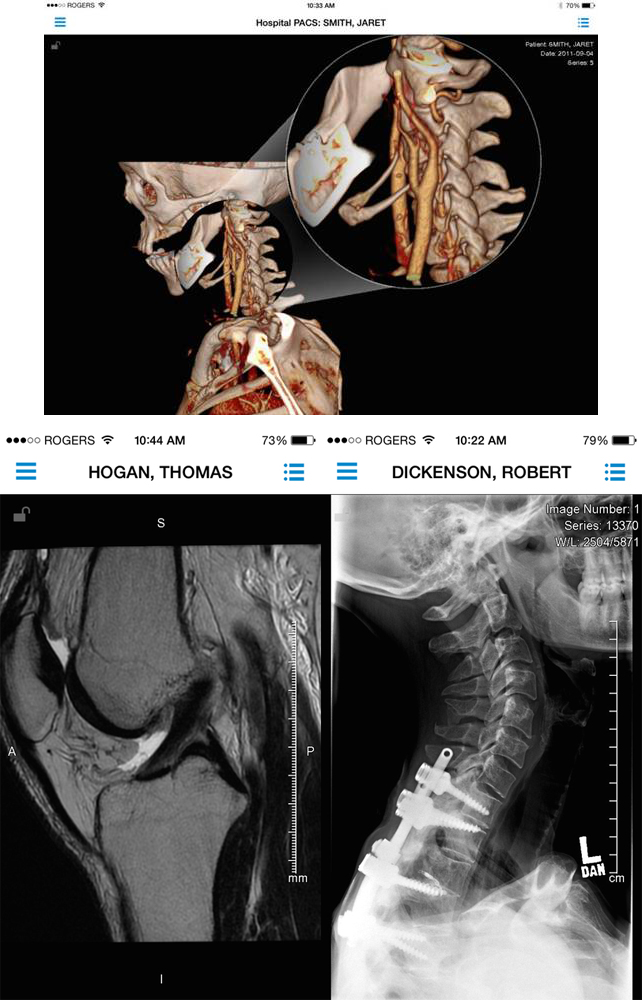

ResolutionMD

一款诊断医疗影像软件,适用于几乎所有图像类型。2014年4月宣布获得FDA认证。能诊断计算机X线摄影,数字摄影,活动影像放射造影,血管造影,超声,核医学,内窥镜和眼科疾病等。该app能帮助医生查看3D图像,同时与其他图片相结合,获取更多诊断信息。Calgary Scientific在2012年的调查研究中发现,在处理中风患者的CT扫描图像中,放射学家利用ResolutionMD移动终端比PACS工作站速度提升了24%,平均每11分钟就拯救一个病人。

功能是让医生安全查看病人的图像和报告,不论来源是电脑或移动设备、还是任何地方的从业人员诊断结果,都能随时随地互动交流。它由FDA认证、加拿大医疗健康认证与欧盟CE认证通过,软件能整合到电子病历系统或已有的储存系统。其他功能有与同行召开视频或音频会议查看图像。另外,有2D的动态展示窗口和3D全互动式导航,具有专业的解剖定位辅导等。该APP还有中国汉化版。